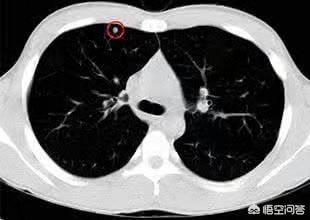

En général, les nodules d'un diamètre supérieur à 8 mm doivent faire l'objet d'une attention particulière, surtout s'ils sont de forme irrégulière, voire accompagnés d'un motif en forme de bavure, ou mélangés avec le réel et l'imaginaire, adjacents à la plèvre et apparaissant comme une dépression pleurale, nous devons être très attentifs à la possibilité d'une tumeur maligne. Si nécessaire, il faut procéder à une ponction-biopsie ou à une excision directe.

Pour les nodules de moins de 8 mm, en particulier ceux de moins de 6 mm, une observation attentive et un examen peuvent être envisagés : la plupart des conditions suivantes sont bénignes, telles que : changements significatifs des caractéristiques du nodule dans un court laps de temps, les bords devenant lisses ou flous, sans lobulation ; la densité du nodule est uniforme ou s'estompe ; et le nodule rétrécit ou disparaît sans augmentation de la densité.

La malignité est principalement envisagée lorsque les changements suivants se produisent, tels qu'une augmentation progressive du diamètre du nodule avec un temps de doublement court, la présence d'un composant solide dans la lésion nodulaire, ou la présence d'un composant solide ou une augmentation du composant solide dans la lésion nodulaire, bien que la lésion nodulaire se rétrécisse.

Premièrement, pour la division des nodules pulmonaires, les nodules pulmonaires ≥8 mm et ≤3 cm sont actuellement appelés nodules pulmonaires typiques, tandis que seuls les nodules pulmonaires <8 mm sont appelés petits nodules !

Deuxièmement, il existe une corrélation entre la taille du nodule pulmonaire et le degré de risque de bénignité ou de malignité ! En général, on considère que les nodules pulmonaires de moins de 5 mm ont un risque de malignité de 0 à 1 % ; ceux de 5 à 10 mm ont un risque de malignité de 6 à 28 % ; et ceux de plus de 20 mm ont une probabilité de malignité beaucoup plus élevée, de près de 60 % ou plus, ce qui est similaire au degré de malignité des nodules pulmonaires de type verre dépoli !